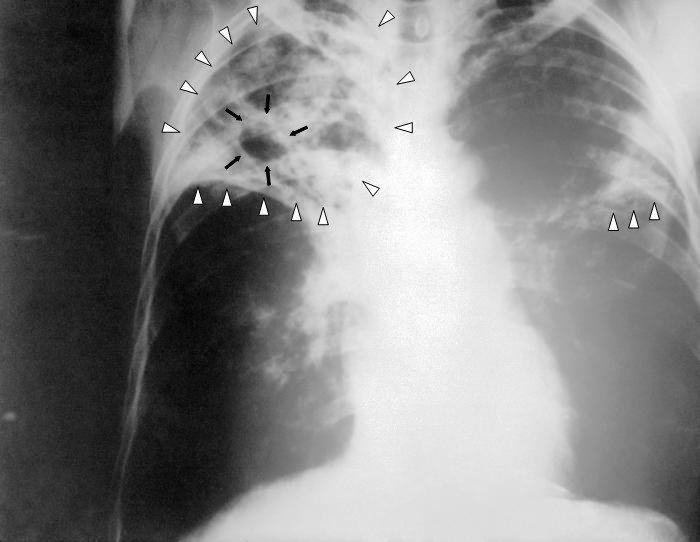

© Фото: CDC Public Health Image Library

Рентгенограмма органов грудной клетки больного туберкулёзом легких с распадом